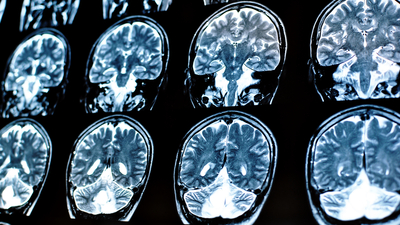

2023'te yayımlanan bir araştırma, yaygın bir uyku ilacının Alzheimer hastalığıyla bağlantılı zararlı proteinlerin beyinde birikmesini azaltabileceğini ortaya koydu. St. Louis'deki Washington Üniversitesi’nde yapılan çalışmada, uykusuzluk tedavisinde kullanılan ‘suvorexant’ isimli ilacın, beyni her gece temizleyen sıvı aracılığıyla Alzheimer ile ilişkili ‘amiloid-beta’ ve ‘tau’ proteinlerinin seviyelerinde hafif bir düşüşe neden olduğu belirlendi.

Araştırma, uyku kliniğinde iki gece boyunca gözlemlenen ve herhangi bir bilişsel bozukluğu olmayan 38 sağlıklı, orta yaşlı yetişkin üzerinde gerçekleştirildi. Bulgular, uyku ve Alzheimer hastalığının biyolojik belirtileri arasında olası bir bağlantıya işaret ediyor.

Bilim insanları uzun süredir uyku bozukluklarının, Alzheimer’ın hafıza kaybı ve zihinsel gerileme gibi belirtilerinden önce ortaya çıkabileceğini düşünüyor. Bu belirtiler ortaya çıkmadan önce beyinde ‘amiloid-beta’ plakları birikmeye başlıyor ve sinir hücrelerinin arasını tıkayarak hastalığın ilerlemesine katkıda bulunuyor.